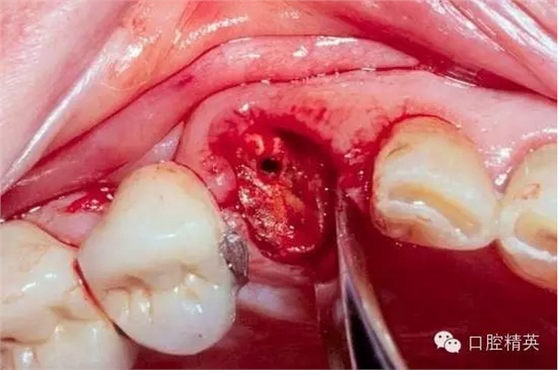

看看一個(gè)雙尖牙根的拔除 ,我常常對(duì)年輕的大夫說(shuō),我覺(jué)得難拔的不是下頜阻生智齒,而是有雙根的上頜雙尖牙,特別是一些正畸需要拔出的健康牙。

拔除后軟硬組織的創(chuàng)傷都很小。